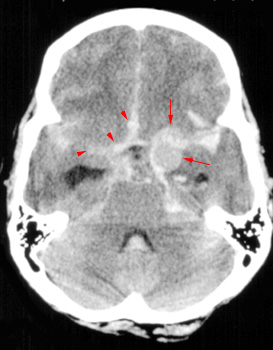

On CT, a subarachnoid hemorrhage appears as high density within sulci

and cisterns. The insular regions and basilar cisterns should be carefully

scrutinized for subtle signs of subarachnoid hemorrhage. Subarachnoid

hemorrhage may have associated intraventricular hemorrhage and hydrocephalus.